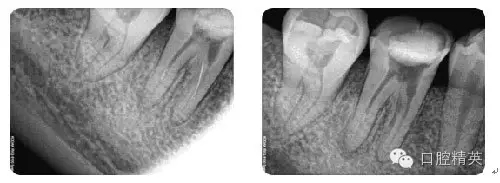

根管治療病例觀賞

病例7:根尖切除術(shù)

病例8:牙周植骨術(shù)